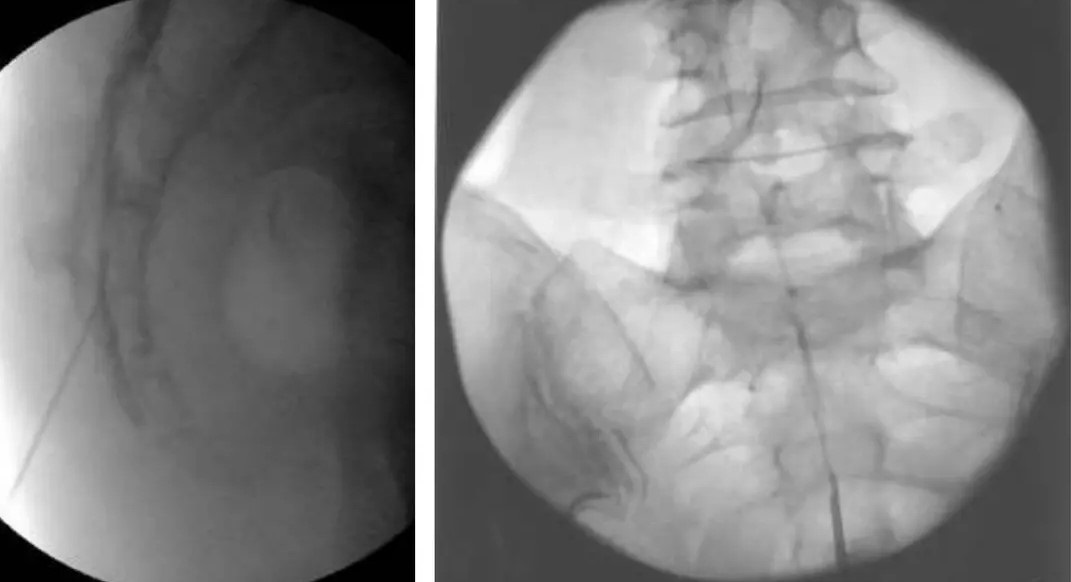

Τι είναι η Ουραία επισκληρίδιος έγχυση

Στην ουραία επισκληρίδιο έγχυση υπό ακτινοσκοπική καθοδήγηση, εισάγεται ένας καθετήρας μέσω του ιερού τρήματος και προωθείται έως το επίπεδο στης κατώτερης οσφυϊκής μοίρας, όπου γίνεται η έγχυση διαλύματος τοπικού αναισθητικού και στεροειδούς.